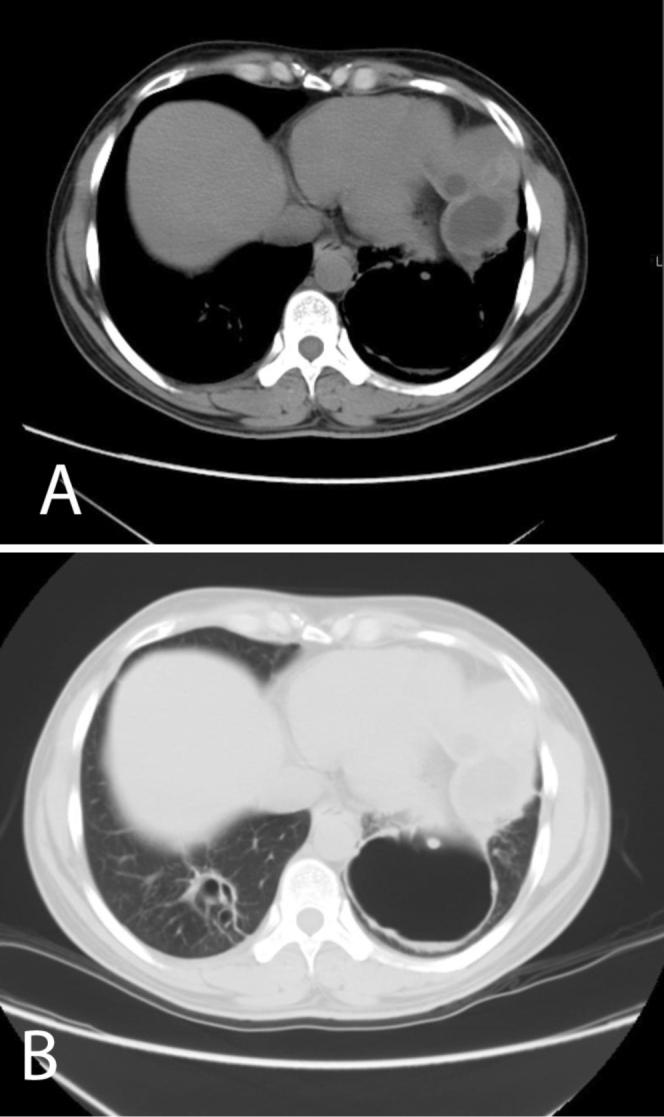

Hydatid cyst is a parasitic infection that primarily affects the liver but which can be found anywhere in the body. This case involves spontaneous dissemination of hydatid cyst disease, a rare occurrence in the absence of any intervention or trauma.

包虫囊肿是一种寄生虫感染,主要影响肝脏,但也可能出现在身体的任何部位。该病例涉及包虫囊肿病的自发播散,在没有任何干预或外伤的情况下,这种情况很罕见。